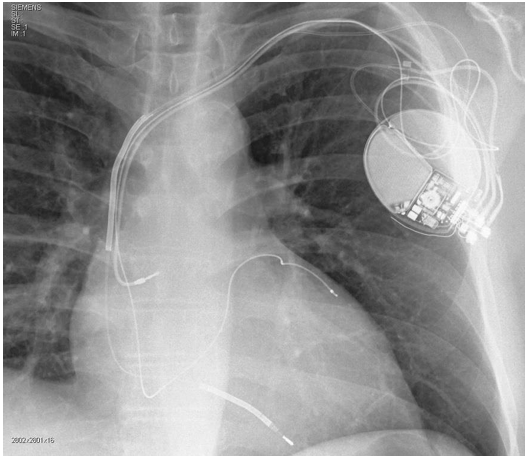

A respeito de pacientes com insuficiência cardíaca sem história de arritmias ventriculares ou síncope, observe a radiografia de tórax a

seguir.

Em pacientes com insuficiência cardíaca sem história de arritmias ventriculares ou síncope, assinale a opção que preencheria critérios para implante do dispositivo presente nessa radiografia.

Em pacientes com insuficiência cardíaca sem história de arritmias ventriculares ou síncope, assinale a opção que preencheria critérios para implante do dispositivo presente nessa radiografia.